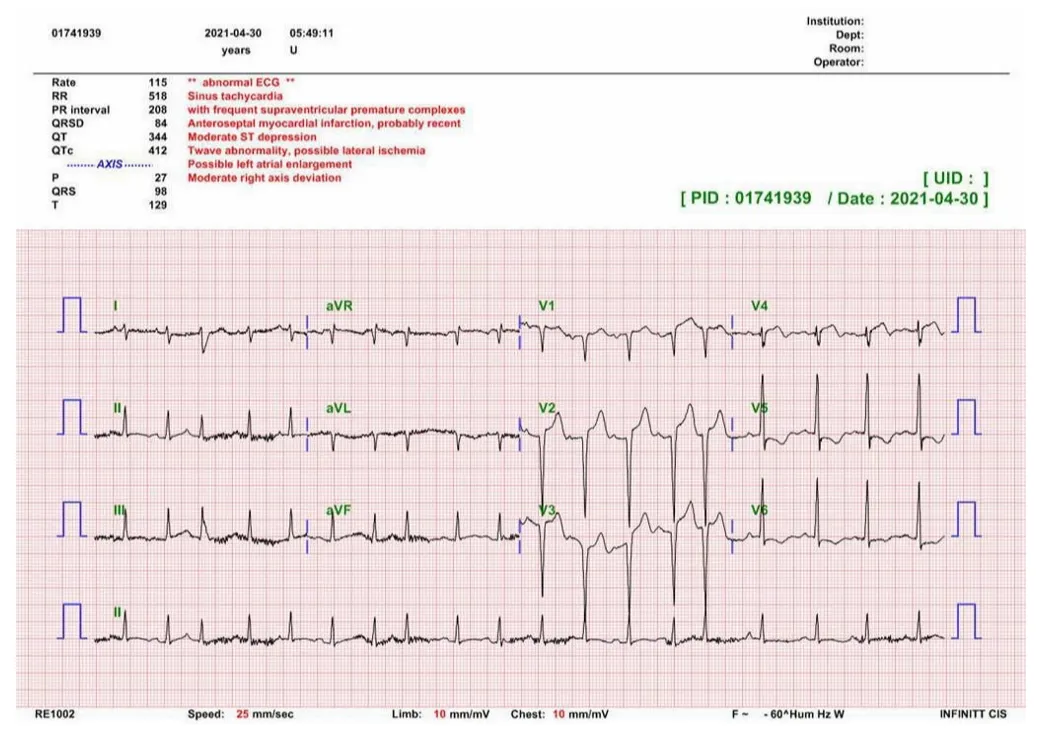

흉통을 주소로 내원한 환자의 EKG에서 ST elevation이 관찰될 때, 15%만이 STEMI가 final diagnosis이다. 따라서 다음과 같은 상황들과 감별해야 한다.

흉통을 호소하는 환자의 심전도에서 ST elevation이 관찰될 때 약15%만이 최종적으로 STEMI로 진단되며 나머지는 심전도상에서 ST elevation이 나타나는 다른 질환들로 최종 진단되며 이러한 현상을STEMI mimics라고 합니다. STEMI mimics을 보일 수 있는 질환들로는 LVH, LBBB, Early repolarization, Pericarditis 등이 있습니다.

<ST elevation에서 acute STEMI를 더 시사하는 소견>

이전 EKG와 비교하여 새로운 ST segment의 변화 & dynamic change

Reciprocal ST depression

Ratio of T wave to QRS complex amplitude

T wave/QRS ratio < 0.36 in all precordial leads : LV aneurysm를 더 시사함

T wave/QRS ratio > 0.36 in any precordial leads : Anterior STEMI를 더 시사함